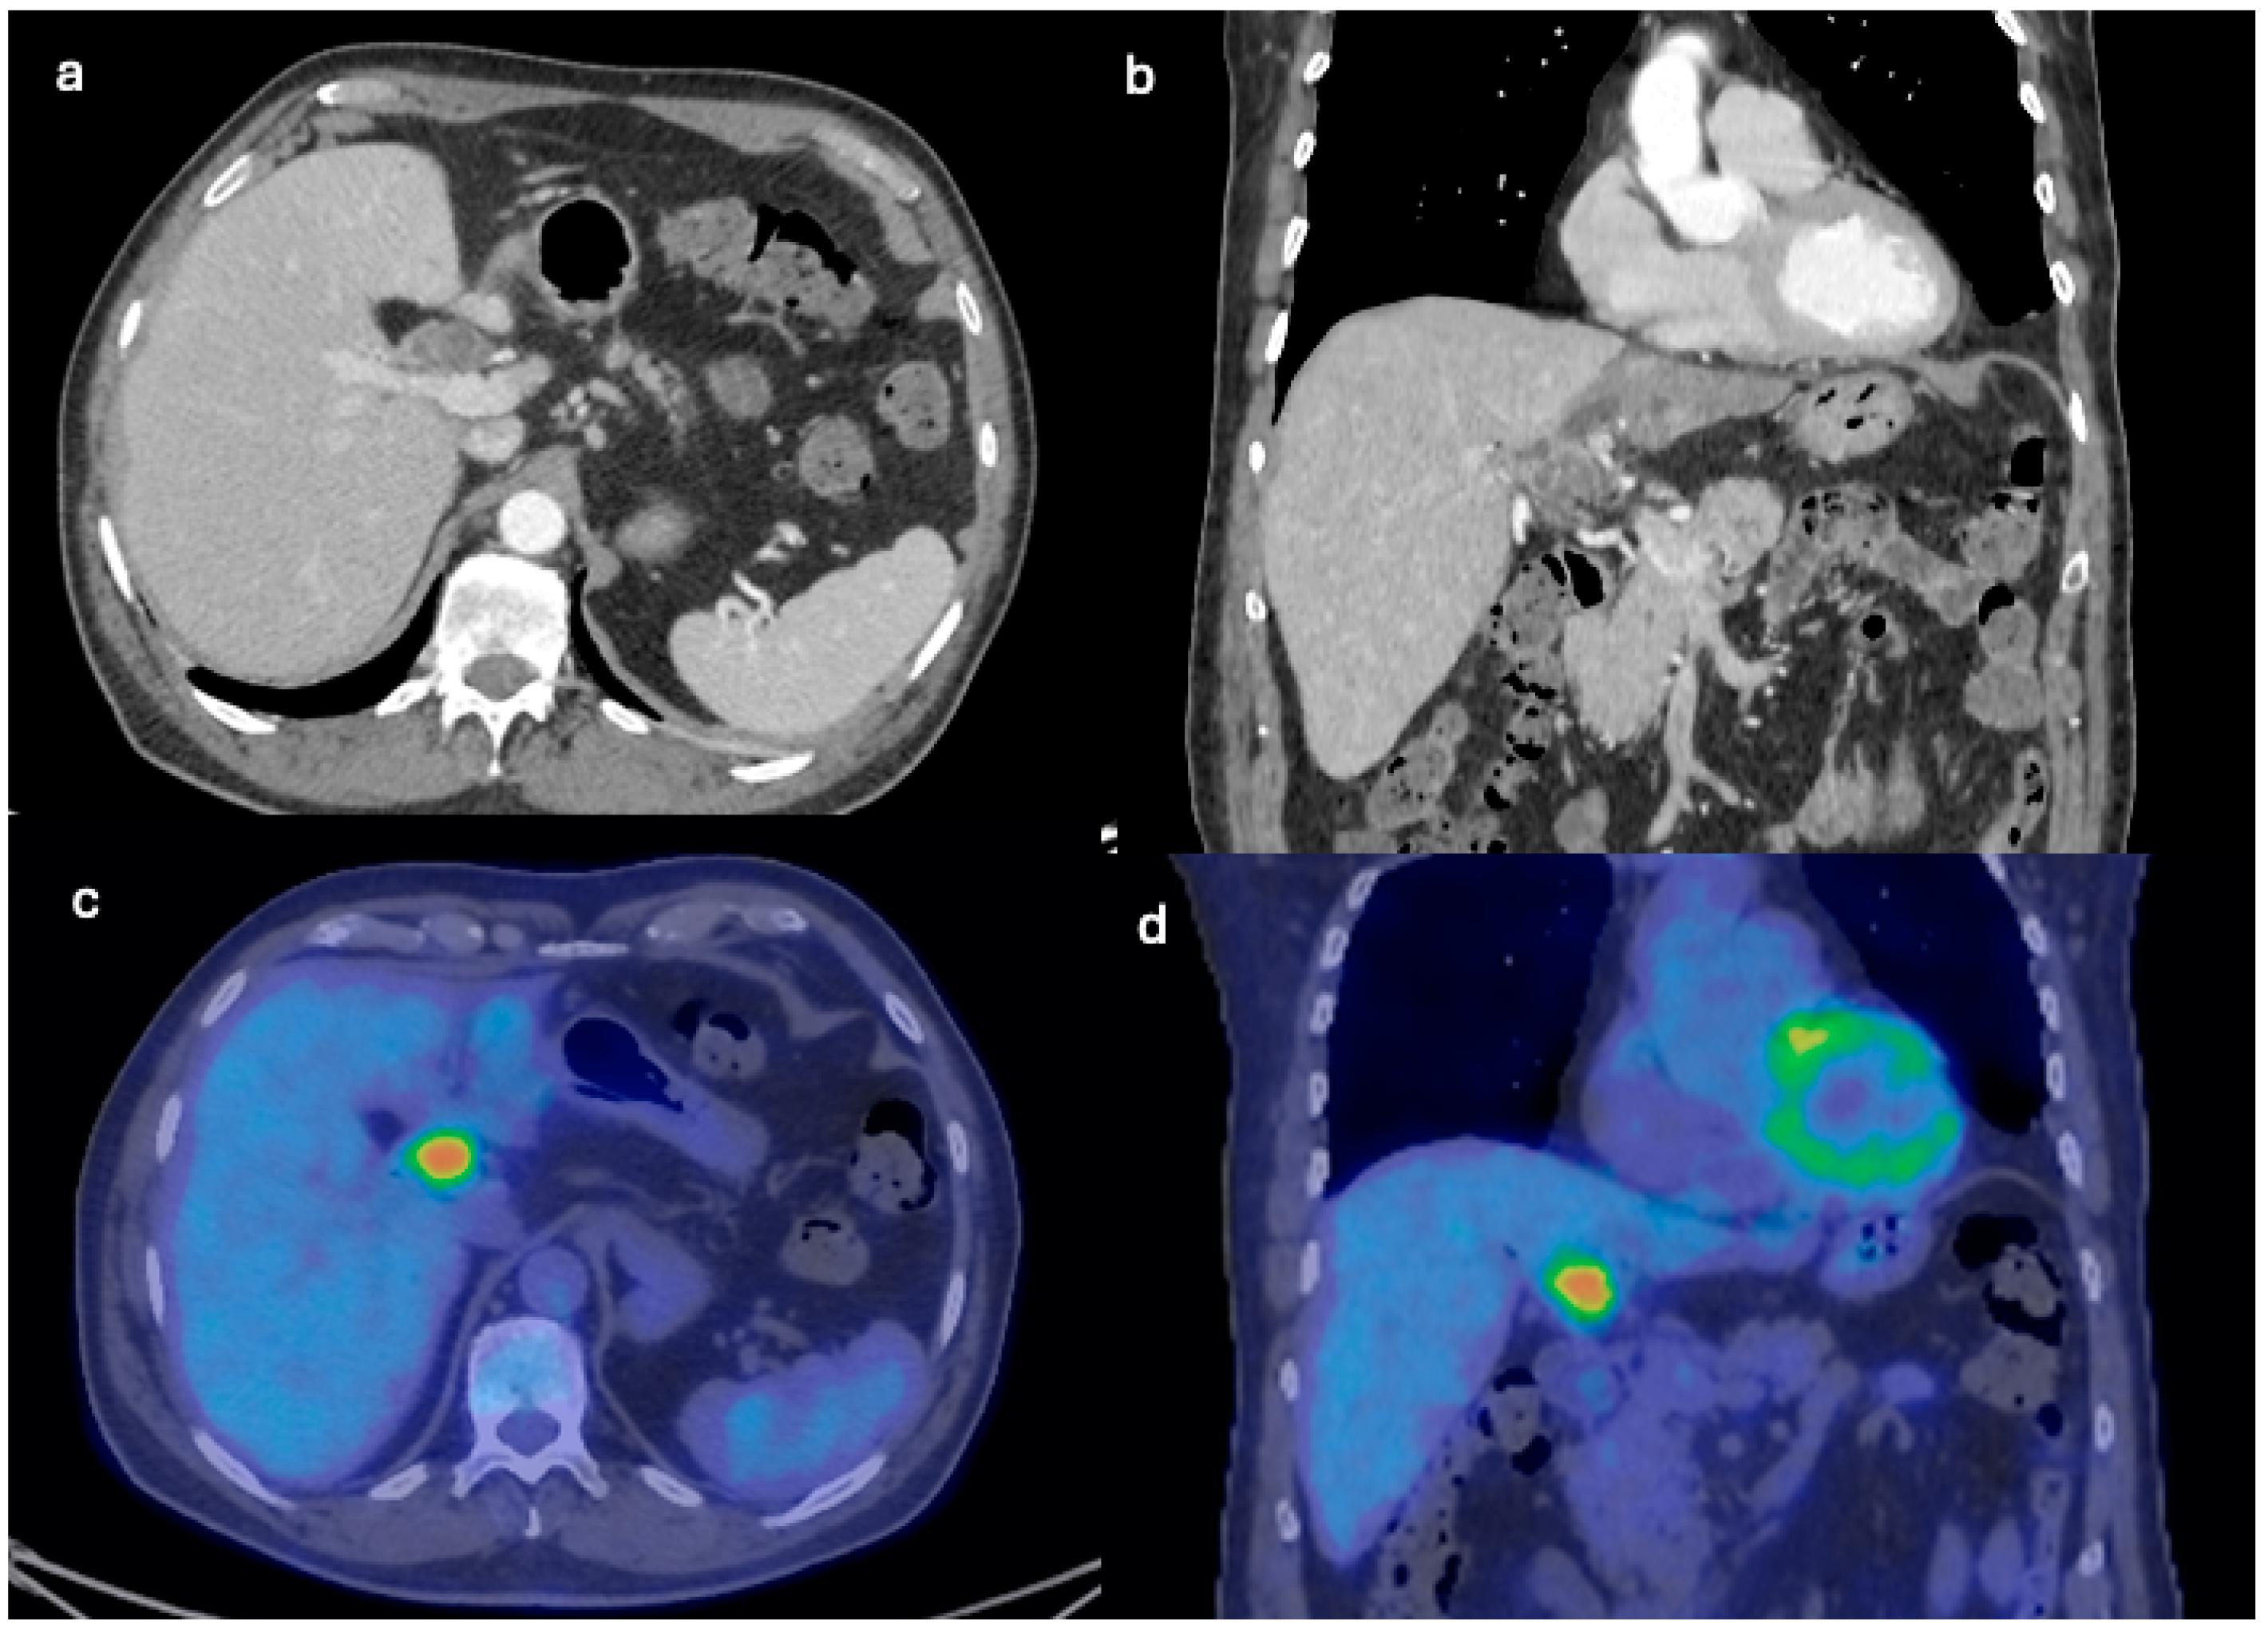

| Initial Diagnosis | Suspected hydatid cyst | Simple cyst, later adenocarcinoma with metastases |

| Diagnostic Methods | MRI, MRCP, ERCP, histopathological examination | CT, MRI, laparoscopic liver biopsy, histopathological examination |

| Tumor Characteristics | Large cystic mass, thin walls, internal septa, papillary projections, enhancing solid components | Large lesion in left hepatic lobe, hyperintensity in T2-weighted images, restricted diffusion, contrast enhancement |

| Treatment | Cyst resection, cholecystectomy | Thrombectomy, chemotherapy, supportive care |

| Surgical Findings | Partially exophytic floating soft mass | Extensive intrahepatic metastases, vascular involvement |

| Histopathological Findings | IPNB with foci of adenocarcinoma, oncocytic appearance, varying degrees of dysplasia, mucus within cyst | Adenocarcinoma with papillary clear cell and mucinous appearance, gland ectasis, cystic or pseudocystic aspects |

| Follow-up and Outcome | Initial recurrence-free survival for 8 years, recurrence treated with left hepatectomy, patient alive at 33 months post-second surgery | Disease progression despite aggressive management, patient died from hepatic failure |